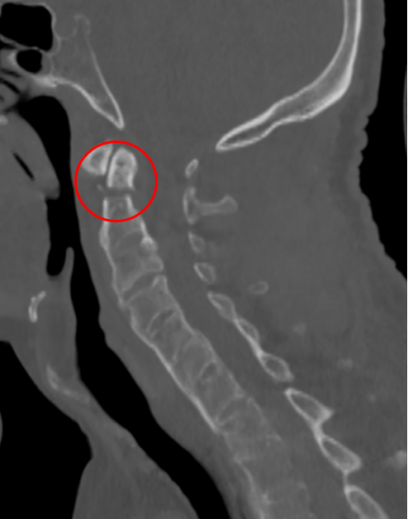

去年,家住昆山的金先生走路的时候不慎摔倒,下颌撞击硬物后感到颈部疼痛难忍,到当地医院查CT显示:(枢椎)齿状突骨折,骨折块向椎管方向移位。齿状突骨折属于上颈椎,位于头颅和颈椎的交界区域,是连接生命中枢的要塞,解剖结构复杂,有椎动脉和中枢神经从中穿过,稍有不慎就会引起大出血、瘫痪、甚至立即死亡。这类手术属于上颈椎手术,曾一度被视为骨科的手术禁区,国内仅有少数医院能够开展这一类手术,一般医师不敢轻易尝试。在业内医师的推荐下,家属送金先生来到了苏州大学附属独墅湖医院,找到了姜为民主任。

接诊后得知,金先生还患有强直性脊柱炎多年,这种疾病直接的后果是脊柱强直如棍棒,骨质变脆易骨折,被冠名以“不死的癌症”。姜主任详细了解金先生的病史后,认为该患者的治疗关键在于以下三个方面:一是脊柱强直,手术部位的位置深难以显露,解剖复杂。二是C2、C3左侧椎弓根发育异常狭小,置入椎弓根螺钉困难。三是齿状突骨折向后方移位明显,通常向前脱位较为常见复位也较容易,此种脱位的复位具有较大的难度和损伤脊髓的风险,对于术者而言是个巨大考验。

金先生伤后第7天,姜主任医师团队在麻醉手术科的密切配合下成功为他实施手术。姜主任凭借多年徒手置钉的过硬技术经验,2小时不到便完成了手术,术中出血仅100ml。术后CT显示齿状突完美复位,螺钉“不偏不倚”的位置恰到好处。术后,金先生在骨科护士长张霞芬护理团队的精心护理下,15天后伤口拆线康复出院。